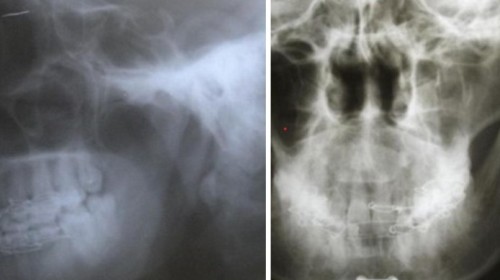

Facial bone reconstruction

During road traffic accidents there are many dental injuries and Facial bone injuries. Because of these injuries patients will have bleeding and deformity of the face and pain. Many people cannot speak and cannot eat properly. So to correct all these things we need surgical procedures.